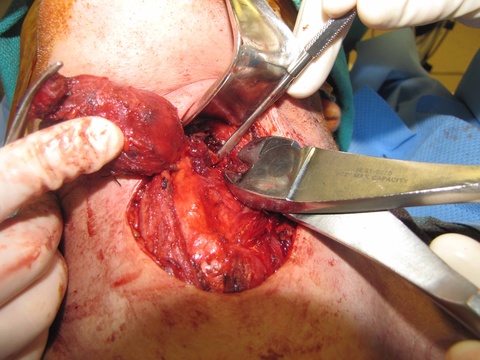

From above, surgeon reached into the mouth and palpated the foramen cecum with the left hand and arm protected with a sterile sleeve and second glove - placed to permit later removal from the contaminated oral cavity to permit continued sterile dissection in a sterile field. With anatomic control directed by palpation intra-orally with concurrent dissection of the open neck, clips were placed to mark the region of the undersurface of the base of tongue where the TGD cyst was to be severed. Final cuts with the bovie were similarly directed both by intra-oral palpation and extra-oral inspection.

Frozen section was taken from the superior most part of the tract - revealing no evidence of a tract. Had there been a tract identified, further dissection (potentially communicating intraorally) would have been done where the hemoclips had been placed above the hyoid (see also: Case example thyroglossal duct cyst with tract through to oropharynx.)

Clinical Images